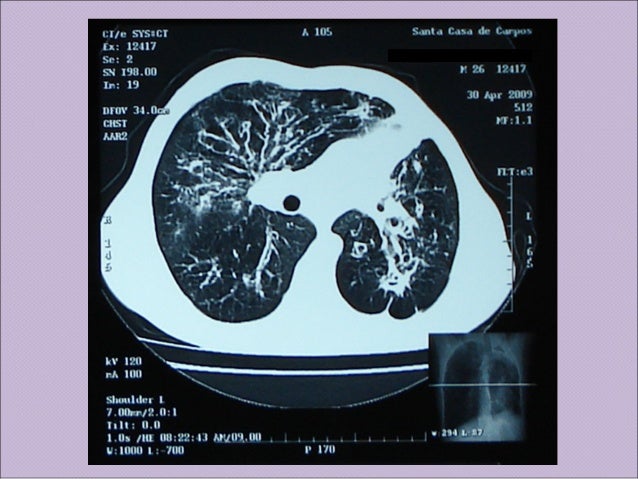

Fibrose cistica

Fibrose cistica from image.slidesharecdn.com